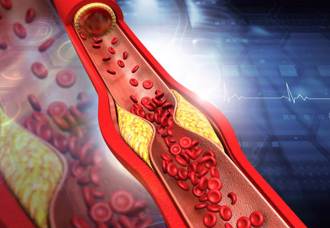

想要活得好、活得久,血管健康非常重要。醫師張家銘指出,血管若失去彈性、硬化,會損傷身體器官、大腦,醫學證實,茶、巧克力、蘋果、帶皮葡萄所含的「黃烷-3-醇」,能修復血管、穩定血壓,還能睡得更好。

現代人生活壓力大,不少男性都會出現精力不足、性功能下降的現象,成為焦慮的源頭。對此,泌尿科醫師高銘鴻指出,除了改變生活方式外,也可從飲食著手,多攝取包括Omega-3脂肪酸、精胺酸、瓜胺酸及維生素D的食物。其中他提到,瓜胺酸參與了體內一氧化氮循環,對於清除血管阻塞物、保護心血管,能發揮正面影響,推薦食物如黃瓜、南瓜、大豆類等。